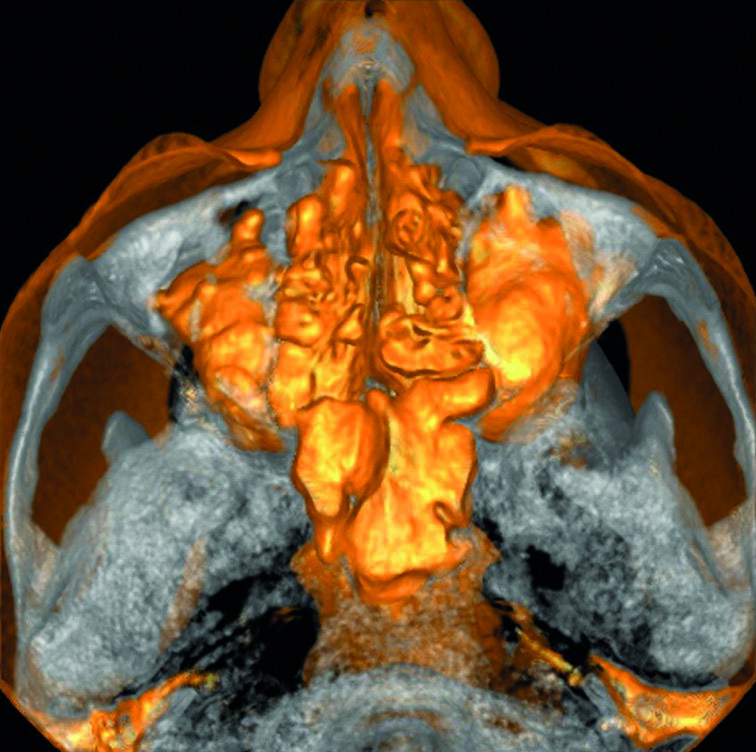

Un patient avait été adressé au cabinet en raison de problèmes associés à la fracture d’une lime. Il était pilote de ligne et se plaignait d’écoulements nasaux purulents lorsqu’il était en vol. La radiographie pré-opératoire (Fig. 1) a distinctement montré la présence de deux fragments d’une lime fracturée dans les canaux mésiaux et d’un cône traversant l’apex de la racine palatine. Après l’imagerie CBCT avec iCAT, il est apparu clairement que le sinus gauche était presque totalement rempli de liquide inflammatoire (Fig. 2) et que le cône présent dans le canal palatin pénétrait dans le sinus. Sur l’image de reconstruction multi planaire (MPR), nous pouvions également distinguer les deux fragments de lime fracturée dans les deux canaux mésiaux (Figs. 3 et 4) et aussi un autre fragment dans le sinus sans aucun contact avec le canal (Fig. 5). L’utilisation de différents filtres nous a permis de visualiser les fragments de lime (Figs. 6–9), ainsi que l’inflammation et le fragment de lime fracturée à l’intérieur du sinus. Nous avons également mieux perçu la position du cône qui émergeait du canal palatin et pénétrait dans le sinus.